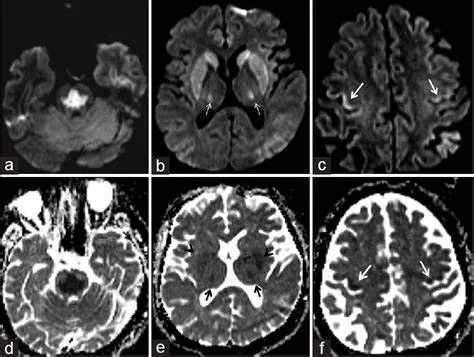

(4)CPM+EPM:(2) (3),MRI 与临床表现不密切相关,一般都会滞后几个星期。

桥脑“三叉戟”+基底核团+丘脑+皮层受累,扩散受限